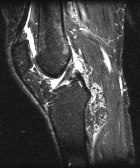

42 year old female with one month of knee pain

Zoom image: Radiological image Radiological image.